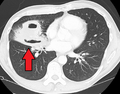

Pulmonary abscess on CT scan

A subpleural abscess.

Lung abscesses are often on one side and single involving posterior segments of the upper lobes and the apical segments of the lower lobes as these areas are gravity dependent when lying down. Presence of air-fluid levels implies rupture into the bronchial tree or rarely growth of gas forming organism.